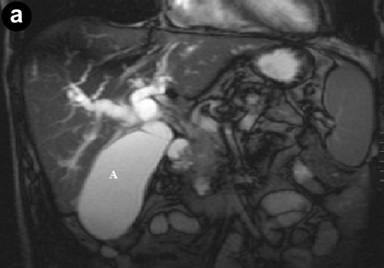

The patient then developed painless obstructive jaundice four months after the procedure. As the clinical features changed and became more sinister, CT scan was repeated, following which a referral was made to the tertiary regional HPB unit. The pre-bypass CT had shown inflammation in the groove with cystic changes in the duodenal wall. A repeat CT at our centre showed a major difference in that there was significant dilatation of the bile duct with a stenosis at the cystic duct insertion site, but the pancreatic duct was not significantly dilated. This was followed by a failed ERCP due to duodenal stenosis hence percutaneous transhepatic cholangiogram and biliary drainage was carried out. MRCP showed a small non enhancing area of low T1 signal within the pancreatic head surrounding the intra-pancreatic common bile duct extending to the ampulla of uncertain significance. CT and MRI scans revealed deleted a soft tissue mass in the head of the pancreas, abutting his superior mesenteric vein (Figures 1 and 2).

|

Figure 2. Pre-operative MRCP. a. Coronal MRCP images illustrating soft tissue mass in head of pancreas and dilatation of the intra and extrahepatic biliary tree. b. Coronal MRCP illustrating intra and extrahepatic biliary duct dilatation. |